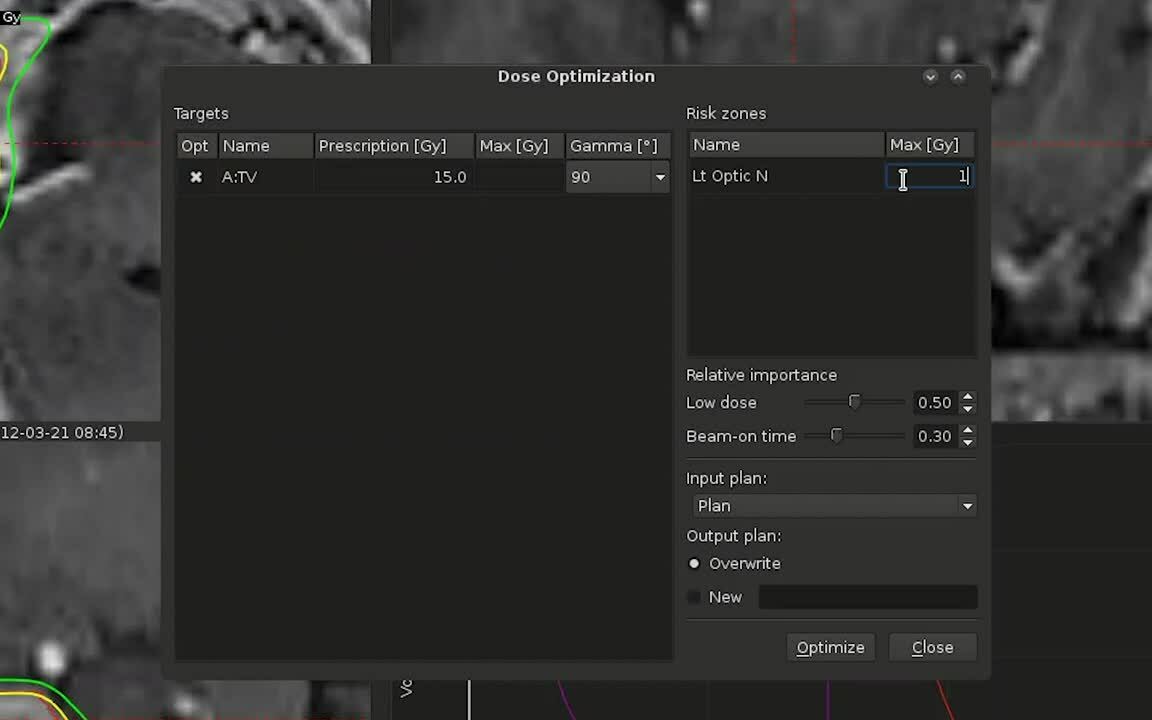

Dose to targets can be optimized very quickly using highly efficient BOT penalties. This results in expertly built plans in less than a minute, providing significant savings in the duration of treatment.

Constraints-based optimization

Multiple and simultaneous hard constraints, such as dose to target and sparing of organs-at-risk (OAR), are introduced for the first time in a practical setting. This facilitates planning for multiple targets and OAR in a single plan, thereby saving a significant amount of planning time.